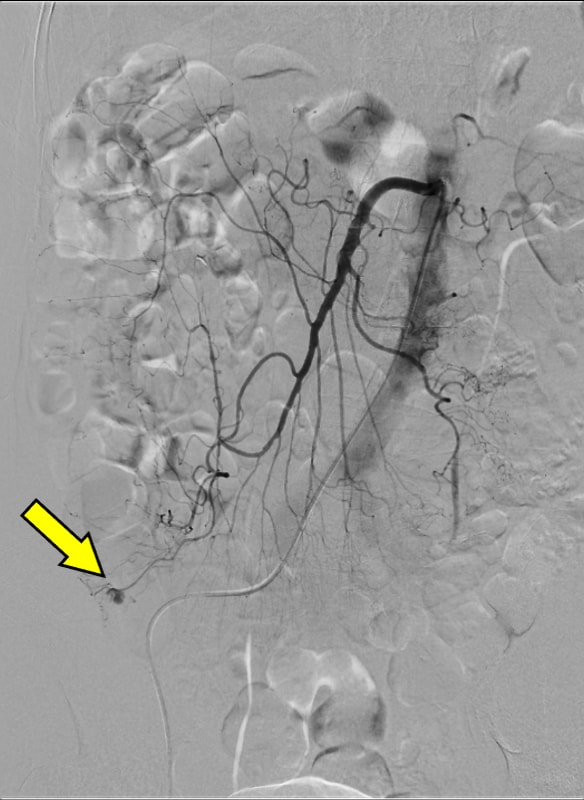

血便があり、当院消化器内科に入院となった。第3病日に下部消化管内視鏡を行うも出血源は不明であった。第4病日に再度血便があり、造影CTを施行すると上行結腸憩室からの活動性出血を認めたため、速やかに緊急TAEを施行した。血管造影で回結腸動脈の分枝からextravasationを認め、責任動脈をコイル塞栓した。術後、再出血、Hb値の低下を認めず、第13病日に退院となった。

PCCTによる高精細な画像はextravasationの検出にとどまらず、責任血管を描出することで標的血管の特定を容易にする。その結果、血管造影での探索時間が短縮され、経カテーテル動脈塞栓術(TAE)の迅速かつ確実な施行につながり、手技の成功率と効率を高めている。